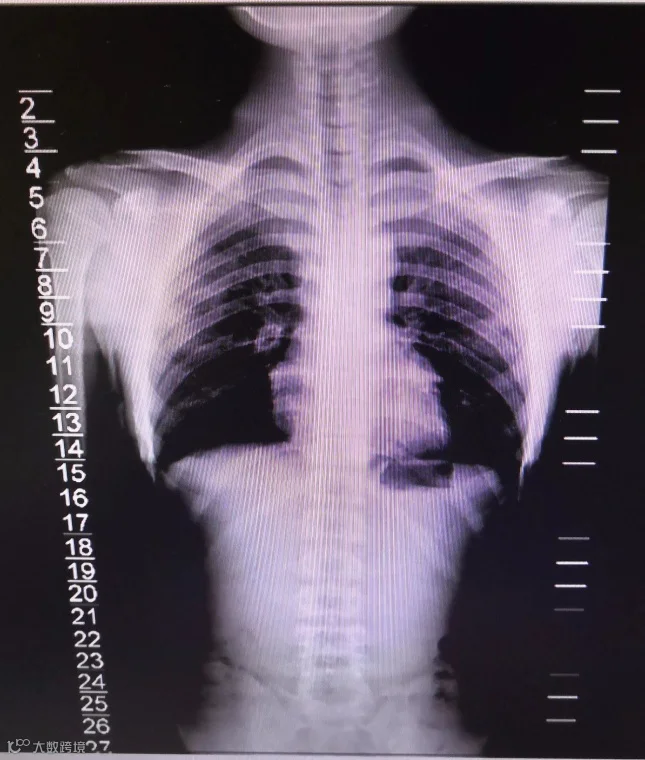

15岁少年脊柱侧弯

科学治疗实现矫正

“脊柱侧弯,又称脊柱侧凸,是指脊柱的某一节段偏离身体中线向侧方弯曲。许多人的脊柱都有一些弯曲,但少数人会出现大幅度脊柱弯曲,呈 S 或 C 形。如果这种弯曲程度很大,则会导致腰背疼痛甚至呼吸困难。”